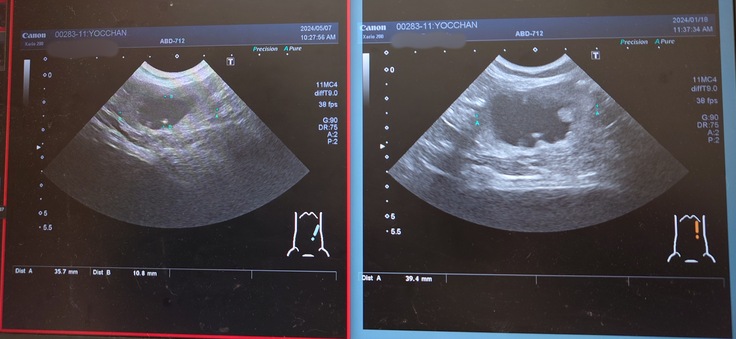

左側の拡大していた尿管。

画像の右側が前回のエコーで、左側が今回のエコー。

でも、尿管拡張していて腎盂腎臓が肥大している左側の尿管が2.1mmから1.1mmに細くなっていてこれは良い結果だったので安心しました😊